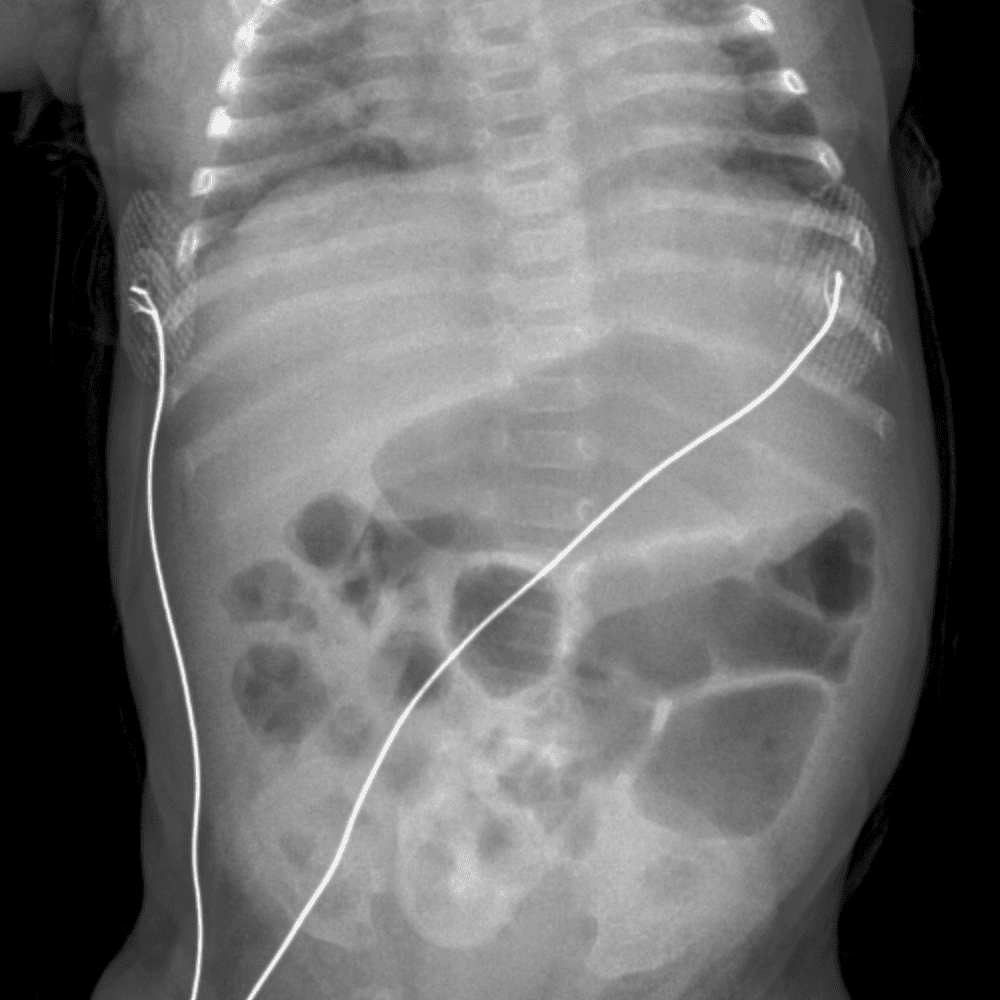

Peds Abdomen

Practice

Simulates call by including subtle or difficult cases and some normals.

30 cases